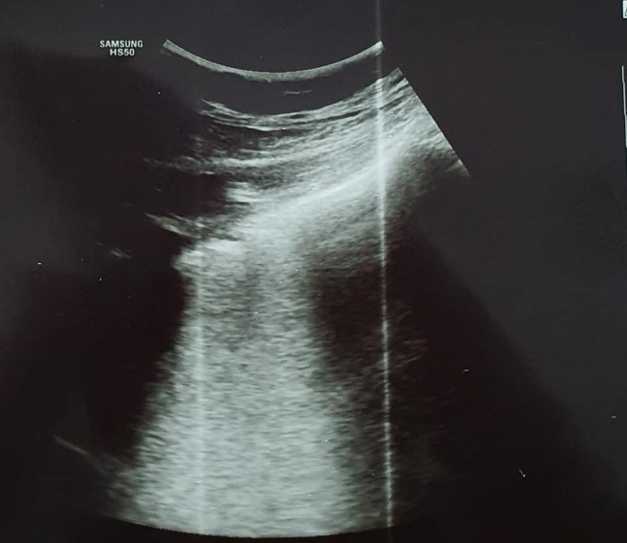

„Imagine de ecografie pulmonară cu o bandă albă în spatele pleurei -Linii B confluente- sugestivă pentru inflamaţia alveolo-interstiţială”, a scris medicul craiovean.